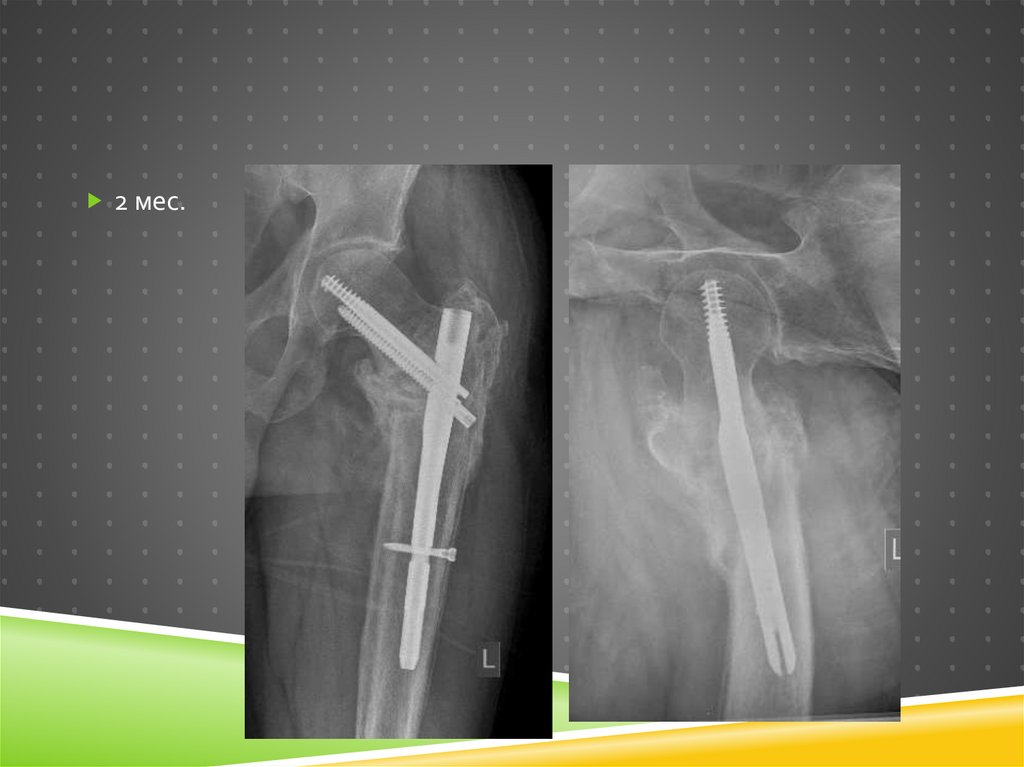

17. Через 2 месяца

ЧЕРЕЗ 2 МЕСЯЦА

Ходит с нагрузкой

на ногу